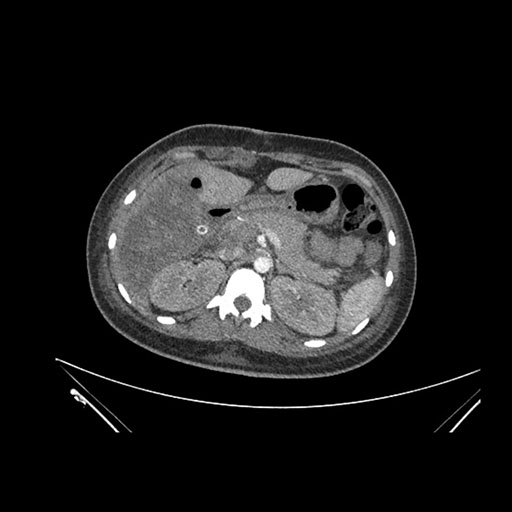

Imaging Analysis

Look through the patient's CT scan to identify any areas of concern for the necessary procedure.

Axial Arterial

Based on initial findings, which issue(s) would you be most concerned about?